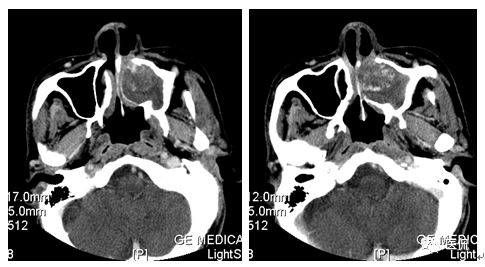

冠状位平扫

CT平扫及增强示:左侧上颌窦及鼻腔可见软组织密度影,呈膨胀性生长,周围骨质压迫性吸收破坏,累及左眶,病灶密度不均匀,周边区可见点状钙化,增动脉期轻度强化,局部见小灶性稍高密度区,静脉期病灶内见不均匀明显强化,CT值最高达117HU,延迟期强化范围有所增大。

影像学表现呈软组织密度,多不均匀,表现为高低混杂密度,病变窦腔内息肉、血肿、坏死、感染共存,是病灶密度不均匀的主要原因,息肉反复出血、血管机化亦为其成因之一。病灶内钙化,可为团块状或小片状,可能为病变组织坏死后钙质沉着所致。由于病变组织内有大量炎性细胞浸润和丰富的毛细血管,增强后常有强化。有文献报道病灶增强中心区强化不明显,外周呈轻度强化,推测病灶内虽然血管丰富,但中心区容易出现血流动力学障碍,血管内常有血栓形成,中心区易发生出血坏死,另外,可能与增强扫描延迟时间选择不当有关。

本例病灶较大,周围骨质可见吸收破坏,并累及眼眶,病灶内少量钙化,增强扫描具有一定特征性,表现为动脉期轻度强化,局部见小灶性稍高密度区,静脉期病灶局部呈明显强化,CT值最高达117HU,延迟期强化范围有所增大,呈延迟渐进性强化的特点,推测为病灶内出血所致。